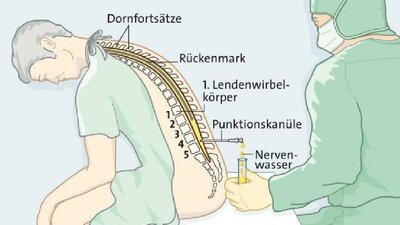

• Lumbalpunktion: Nervenwasser aus dem Rückenmarkskanal

Bei einer Lumbalpunktion gewinnt der Arzt das sogenannte Nervenwasser (Liquor), das Gehirn und Rückenmark umhüllt. Dafür sticht er im Bereich der Lendenwirbelsäule eine sehr dünne Hohlnadel in den so genannten Duralsack. Dieser befindet sich im Inneren des knöchernen Wirbelkanals, umschließt das Rückenmark und ist mit Nervenwasser (Liquor) gefüllt. Bei einer diagnostischen Lumbalpunktion zapft der Arzt eine kleine Menge Nervenwasser ab, um es im Labor untersuchen zu lassen.

Darüber hinaus nutzen Mediziner das Verfahren aber auch zur Behandlung: Bei einem sogenannten Normaldruckhydrozephalus produziert der Körper mehr Nervenwasser, als er wieder aufnehmen kann. Dann ist die Ableitung des überschüssigen Nervenwassers eine sinnvolle Maßnahme. Außerdem können Ärzte zur Schmerzstillung bei einem chirurgischen Eingriff oder während einer Geburt auf diesem Weg Medikamente verabreichen.